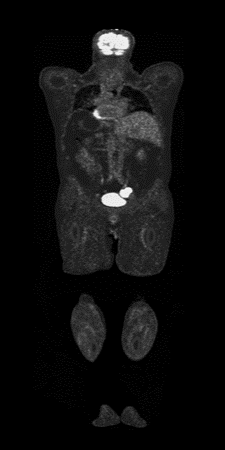

As part of our study, we conducted a comparative analysis of the effectiveness of three different one-step segmentation methods. The experiment utilized three models: U-Net architecture, UNETR, and nnU-Net, a dedicated framework for image segmentation. The models were trained on two datasets. The first dataset contained all images of the initial dataset, while the second dataset was reduced by negative control cases in which there was no case of cancer. The second part of the study was to perform two-step segmentation on the U-Net model. The models’ effectiveness was evaluated using two indicators: the Dice similarity coefficient and the aggregated Dice similarity coefficient. The obtained results are presented in Table 1. The evaluation was performed on a separate test set from the original dataset included images with cancerous lesions. Exemplary visualizations of the obtained results are shown in Figure 2.

Refer to caption

Figure 2: Visualization of the most accurate segmentation (DSC: 0.94) for various nnU-Net configurations trained on the tumor-only dataset. The ground truth tumor is marked in blue, while the model predictions are marked in red, orange, green, and yellow.